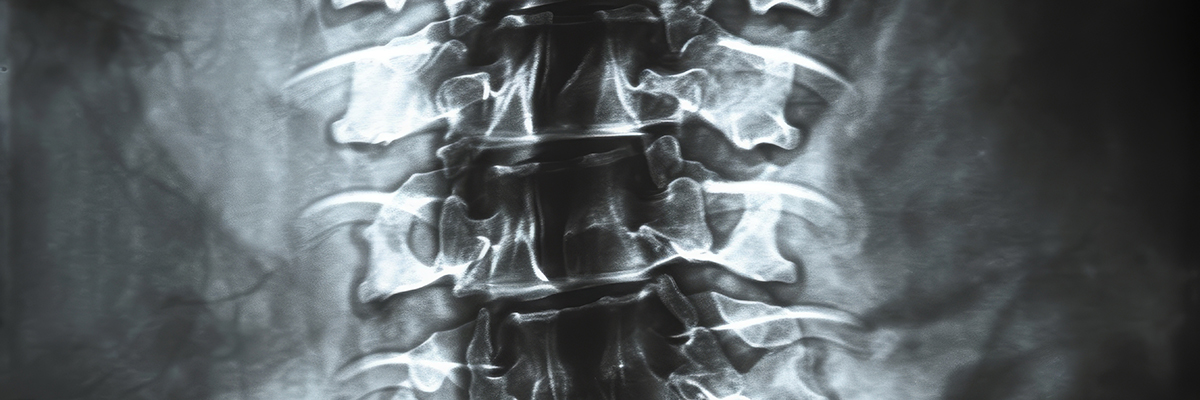

The UAB Department of Orthopaedic Surgery Spine Section is a center of excellence in patient care and provides comprehensive services to a full range of pathologies. The research in spine surgery is led by three fellowship-trained spine surgeons who investigate a wide range of conservative and surgical treatments. The section also collaborates with multiple departments across UAB to advance spine research.

The Spine Section further provides opportunities for medical students, residents, and fellows to be involved in research studies. Overall, our spine research aims to improve patient outcomes with spine surgeries as well trying to find new solutions to complex pathologies. Our research interests include low back pain, neck pain, spinal fusions, spinal cord injury, spinal deformity/scoliosis research, and spinal tumors.